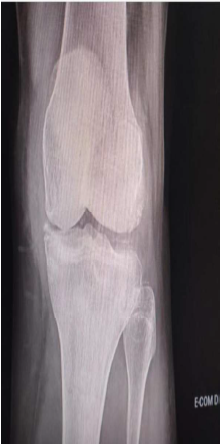

Paciente de 72 anos procura o pronto atendimento com quadro de dor intensa e limitante em joelhos há 48 horas.

Relata episódios prévios de dor e inchaço em joelhos e no punho direito. Ao exame clínico apresenta artrite de joelho esquerdo com derrame volumoso e calor. Abaixo, a radiografia realizada no pronto atendimento.

Com base no quadro clínico descrito e a imagem fornecida, marque a opção correta quanto à hipótese diagnóstica mais adequada.